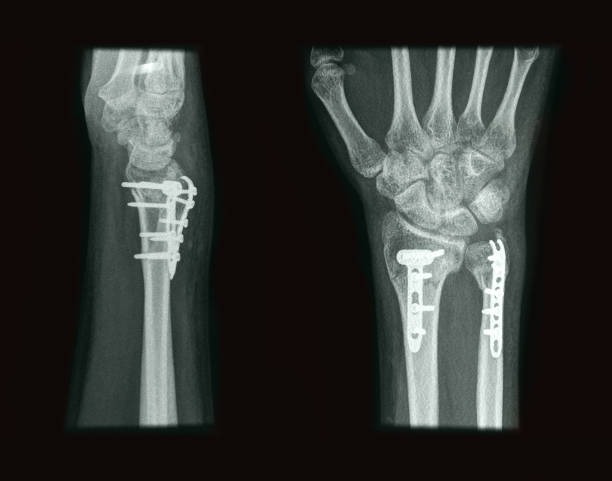

해부학적 이상은 척골충돌증후군의 주요 원인 중 하나로, 팔꿈치와 손목 사이의 뼈 구조나 관절 배열에 선천적 혹은 후천적 변형이 있을 때 발생할 수 있습니다. 예를 들어, 척골이 정상보다 길거나 뼈의 돌출부가 비정상적으로 발달하면 손목과 척골 사이의 공간이 좁아져 충돌이 발생하기 쉽습니다. 이런 구조적 이상은 일상적인 움직임에서도 반복적으로 뼈와 인대, 힘줄 사이에 마찰을 일으켜 염증과 통증을 유발합니다. 해부학적 이상은 개인마다 다르게 나타나며, 증상이 심하면 기능 저하와 만성 통증으로 이어질 수 있습니다. 정확한 진단을 위해 X-ray, MRI 등의 영상 검사가 필요하며, 치료는 보존적 방법부터 수술적 교정까지 다양하게 적용됩니다. 조기에 이상을 발견하고 적절한 관리와 운동으로 관절의 움직임을 개선하는 것이 중요합니다.

손목 및 팔꿈치 외상은 척골충돌증후군 발생에 중요한 역할을 합니다. 넘어지거나 충격을 받았을 때 손목이나 팔꿈치에 직접적인 타격이 가해지면 뼈나 연골, 인대가 손상될 수 있습니다. 이러한 외상은 관절 내 공간을 좁히거나 염증을 유발해 척골과 손목뼈 사이의 충돌 가능성을 높입니다. 특히 골절 후유증이나 인대 파열은 관절 안정성을 떨어뜨려 반복적인 마찰로 만성적인 통증과 운동 제한을 초래할 수 있습니다. 외상 후 적절한 치료와 재활이 이루어지지 않으면 척골충돌증후군으로 진행될 위험이 높아집니다. 따라서 초기 외상 발생 시 전문의의 정확한 진단과 치료, 꾸준한 물리치료가 중요하며, 손상 부위의 기능 회복과 통증 완화에 초점을 맞추는 것이 필요합니다.

골절 후유증은 뼈가 부러진 후 적절히 치유되지 않거나 회복 과정에서 문제가 생겨 나타나는 다양한 합병증을 의미합니다. 골절 부위가 제대로 맞지 않으면 변형이 발생하거나, 뼈가 유합되지 않는 불유합 상태가 될 수 있으며, 이는 통증과 기능 저하를 초래합니다. 또한 주변 인대나 근육, 신경 조직이 손상받아 운동 범위 제한과 근력 약화가 나타나기도 합니다. 특히 관절 근처 골절의 경우 관절 기능 장애가 심해지기 쉬워 일상생활에 큰 불편을 줄 수 있습니다. 감염이나 혈액 공급 장애로 인한 골괴사도 후유증으로 발생할 수 있으며, 재활 치료와 지속적인 관리를 통해 기능 회복을 도모해야 합니다. 골절 후유증을 예방하려면 초기 적절한 치료와 꾸준한 물리치료, 그리고 정기적인 추적 검사가 필수적입니다.